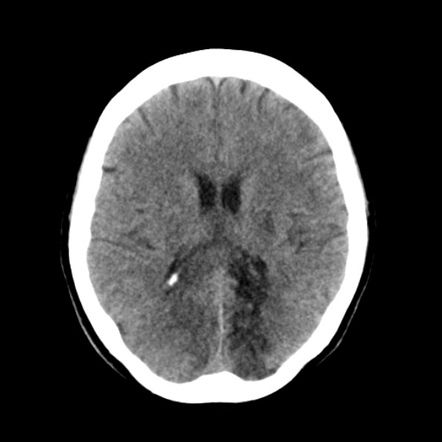

뇌경색 전조증상과 대처방법 및 치료 방법

원인

뇌경색 전조증상은 일시적인 뇌혈류 저하가 원인입니다. 이는 대개 혈압이나 혈관 질환, 고지혈증, 당뇨병, 과음, 금연 등의 생활 습관 등이 원인일 수 있습니다.